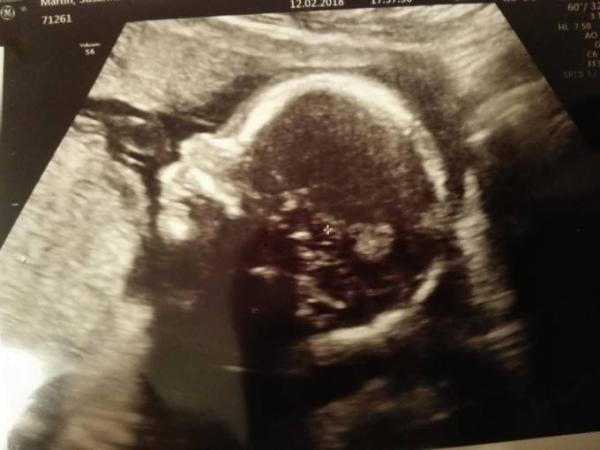

Wir waren heute Abend auch beim Frauenarzt. Es hat es sich mit dem Po nach unten bequem gemacht und relaxte mit einer Hand hinter dem Kopf. Zum Glück nicht vor dem Gesicht. Da haben wir ein recht süßes Profilbild bekommen. Es war etwas schwierig, dass Geschlecht zu sehen. Aber letztendlich sah man nichts. Wir bekommen also unser Mädchen. Die Ärztin hat extra noch einmal vaginal geschallt, um ganz sicher zu sein. Es soll wohl nach der Messung so 180 g auf etwa 20 cm wiegen. Aber da legte sie sich nicht so fest. Ich habe übrigens auch eine Vorderwandplazenta, was mich wundert, da ich es ja schon seit der 11. SSW spüre (anfänglich natürlich nicht regelmäßig). Aber vielleicht eine Erklärung dafür, dass mein Partner es noch nicht spürt.. Eben hab ich aber mal geschaut, als es sich bewegt hat. Da konnte ich es auch von außen sehen, dass sich die Bauchdecke hebt. Meinen nächsten Termin habe ich dann Ende April. Zwischendurch noch die Feindiagnostik und halt die Vorsorgen bei meiner Hebamme. Irgendwas wollte ich euch noch fragen. Vielleicht fällt es mir später wieder ein. Wünsche euch noch einen schönen Abend.

Bild zu Tendenzbestätigung - Forum für Juli - Mamis

Ohh wie süß, ein sehr schönes Bild habt ihr da bekommen

Was für ein süßes Bild. Herzlichen Glückwunsch zur Prinzessin . Habt ihr schon Kinder?

Wow! Was für ein tolles Profil Ich wasche sogar manchmal 90 Grad. Gerade Handtücher, Sportklamotten usw. Auch Babies‘ Klamotten werde ich sicher bei 60 Grad mal waschen. Übrigens, ich habe auch eine vwplazenta. Aber tangiert mich nicht sonderlich